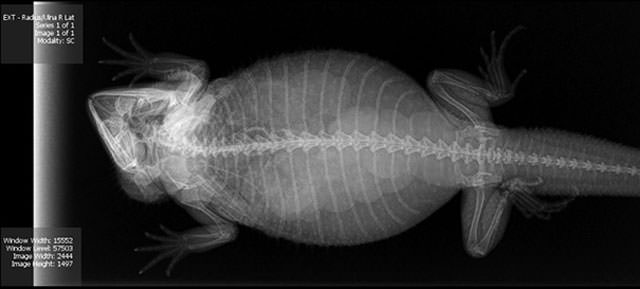

Kaplumbağa